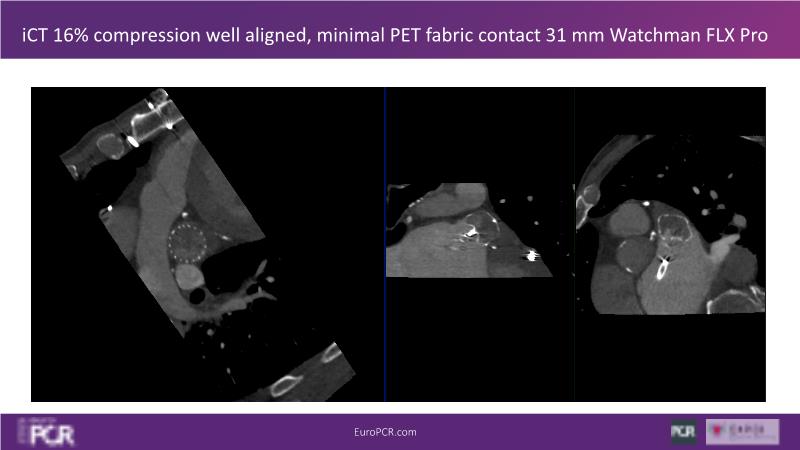

Explore this session to discover the latest innovations in interventional cardiology images, including the benefits of artificial intelligence and angio-CT in PCI/SHD procedures. Learn about Alphenix Evolve and the initial experiences with AI imaging in daily cathlab practice, alongside intraprocedural angio-CT guided LAAO, and engage in discussions on meaningful tools that can transform patient care.